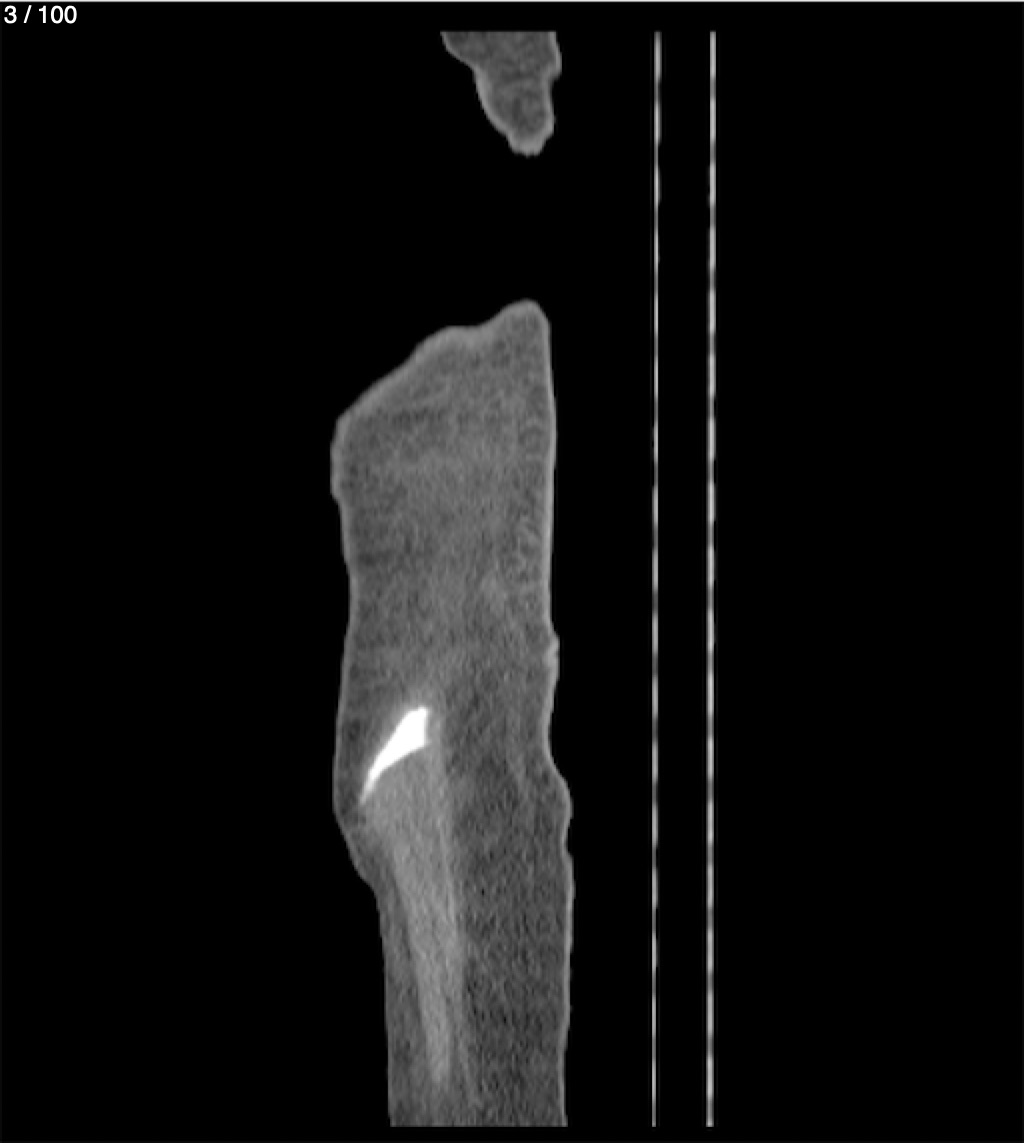

Hilda Geronimo Mendez 60A - T.C Abdomen Simple